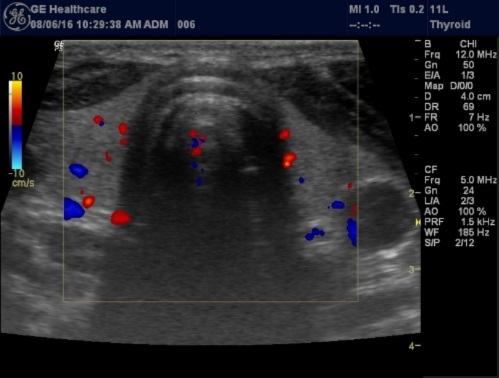

Color Doppler may be used to study the blood flow pattern of the thyroid gland, Figure 2. Thyroid blood flow may increase in some thyroid disorders like Graves' disease.

Figure 2.Blood flow pattern in normal thyroid gland

Blood flow pattern in normal thyroid gland

Histologically, if the excised gland has volume <500 mm3 it is said to be hyperplastic and if the volume is more than 500 mm3 it is nodular hyperplasia in 80% of cases26. In secondary HPT, the increase in the volume of parathyroid glands is associated with increase in vascularity, as evident in Color Doppler imaging 27.